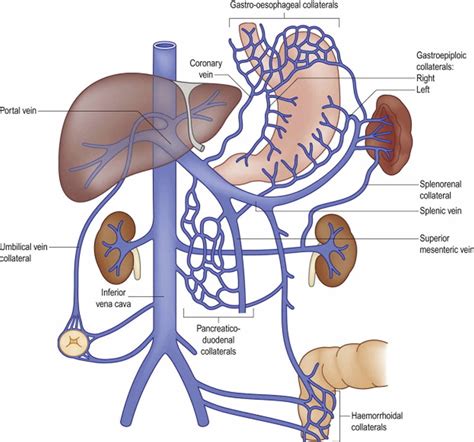

In contrast, chronic PVT is often asymptomatic initially, as the body attempts to form collateral vessels (bypass routes for blood) to compensate for the blockage. However, over time, the resulting portal hypertension can cause complications such as:

• Variceal Bleeding: The pressure buildup forces blood into smaller veins in the esophagus or stomach, which can rupture and cause life-threatening gastrointestinal bleeding.

• Splenomegaly: Enlargement of the spleen due to blood backing up into it.

Ongoing care generally involves regular imaging studies to monitor the status of the thrombus and the development of collateral circulation, as well as periodic endoscopies to screen for esophageal varices. Maintaining close communication with a specialist, typically a hepatologist, ensures that any new symptoms are addressed quickly and that the treatment plan remains optimized for the patient’s changing health status. With proactive management and adherence to medical advice, many individuals can effectively manage the condition and lead active, productive lives, minimizing the impact of the thrombosis on their daily well-being.

• portal vein anatomy